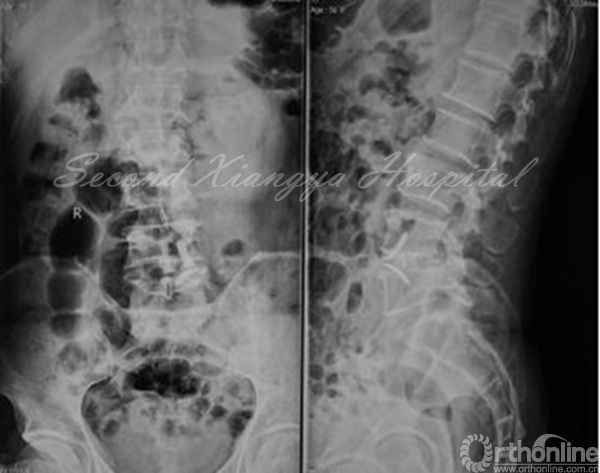

X线:动力位显示腰椎不稳。

术前正侧位片

动力伸位、动力屈位